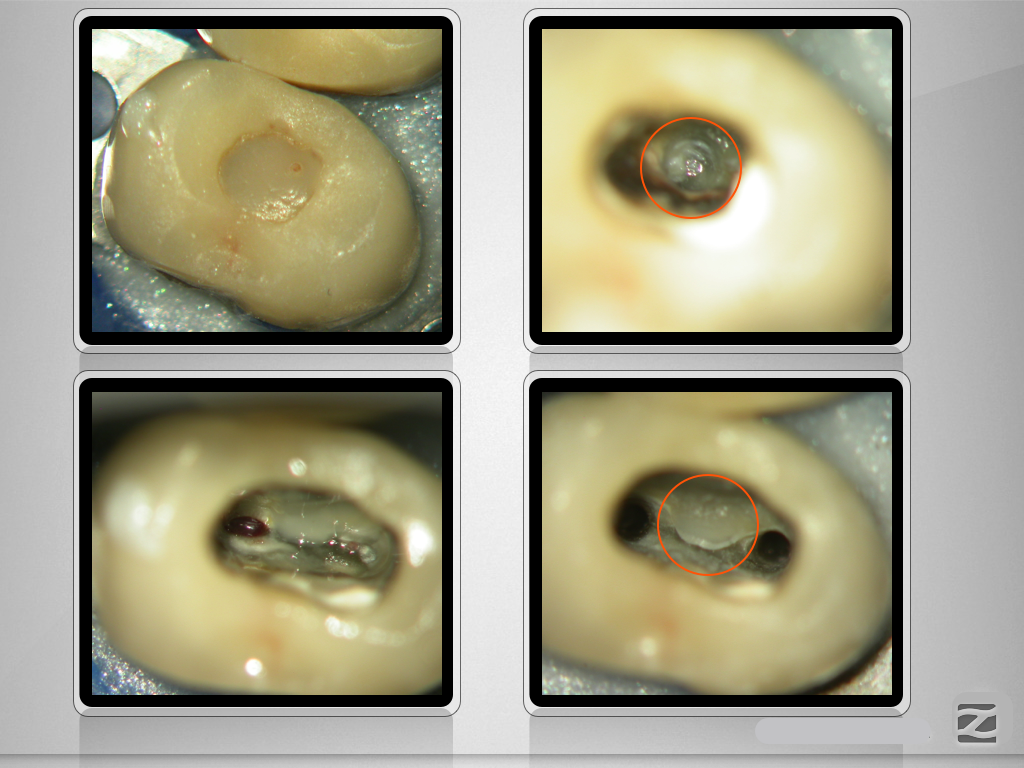

Die Offensichtigkeits-Gefahr